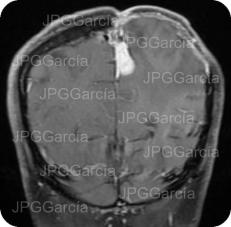

Estudio de IRM de cráneo (Contraste) como control postquirúrgico en donde se observa residual de meningioma anexo a la hoz cerebral el cual fue sometido a radioterapia